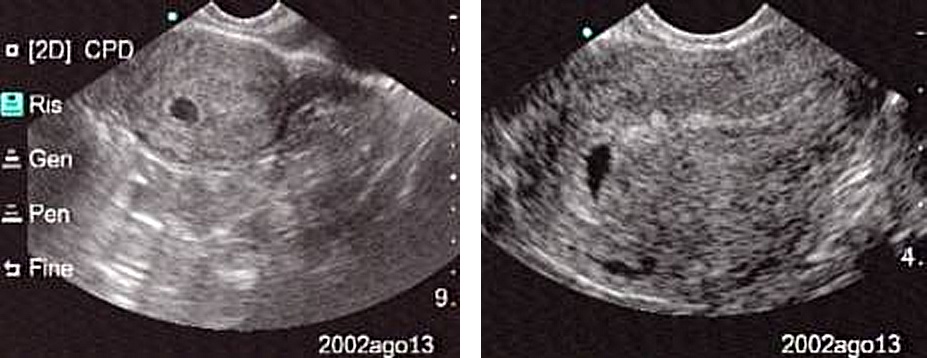

La massa bianca é il sacco amniotico pieno di liquido che circonda l'ovulo concepito che diventa poi embrione e feto. Questo si trova nella cavità blu marcata di lila. Fino alla 4. settimana tutto è bianco. Nella quinta si vede la cavità blu senza niente dentro. Nell'ecografia in questione vediamo che nella cavità blu ci sono 3 "isolotti" di materia, caratteristica della 6. alla 7. settimana. All' ottava settimana i 3 "isolotti" si sono fusi in una massa compatta più grande. Dall'inizio fino all'ottava settimana un aumento da 2 mm a più di un centimetro. Si tratta quindi de entità piccolissime ma già umane. Il cuore batte dalla sesta settimana. Un cuoricino minusculo, microscopico.

Rivedendo la data dell'ecografia nell'angolo in alto a destra, si vede il giorno, il mese e l'ora, però l'anno è stato mutilato. Caso mai è un ecografia tratta dall'internet e "preparata" dalla bielorussa.

Lasciate perdere @mondokane che racconta cose a vanvera.

La camera gestazionale è visibile a volte anche dalla 3 settimana, e sicuramente dalla 4 settimana è ben visibile,

Quella dell'ecografia messa online da Viaggiatore è una camera gestazionale minuscola (va tenuto presente che è un'ecografia transvaginale, e il campo visivo totale dell'immagine è un'area molto piccola di utero) quindi va benissimo per essere della 3/4 settimana.

Tenete presente che la camera gestazionale cresce di 1 mm al giorno, quindi la frase di mondokane "è evidentissimo che si tratta della sesta alla settima settimana di gravidanza a partire la data d'inseminazione" è una cacata pazzesca..

Inoltre è sbagliata la sottofrase "settimana di gravidanza a partire (dal)la data d'inseminazione". Le settimane di gravidanza si contano a partire dall'ultima mestruazione. Quindi l'inseminazione è avvenuta 10-14 giorni dopo (e la fecondazione 14 giorni dopo).

Se indichi la luna i fessi guardano il dito... Si possono dire tante cose su questa storia, tranne che non sia possibile avere la certezza di gravidanza con un'ecografia alla 3 settimana. Inoltre l'ecografo oltre alla presenza della camera gestazionale (che c'è) riconosce anche l'aumento di dimensione dell'utero e l'inspessimento dell'endometrio.

Allego a titolo d'esempio un'ecografia alla 3 settimana con camera gestazionale ben visibile.

Adesso però ci sei cascato anche tu, L'ecografia a sinistra con la chiazza interamente nera é della quinta settimana e non della terza!